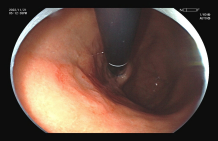

图示:食管早癌在内镜下NBI观察呈片状褐色改变,ME-NBI观察,微血管扭曲、紊乱